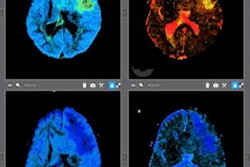

NeuroQuant measures brain atrophy by assessing the size of the hippocampus and other brain structures that typically deteriorate with neurological disorders, the company said. The software then compares the results with those from people who are the same age and have healthy brains, according to RadNet.